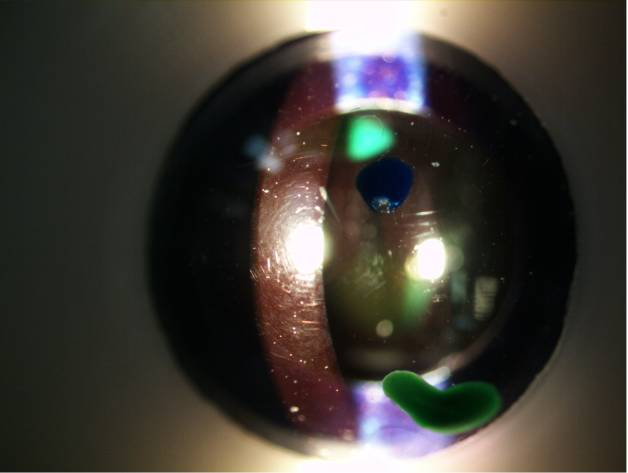

what abnormality is visible in this picture

iris transillumination

which layer of the cornea is the green lesion located in?

endothelium